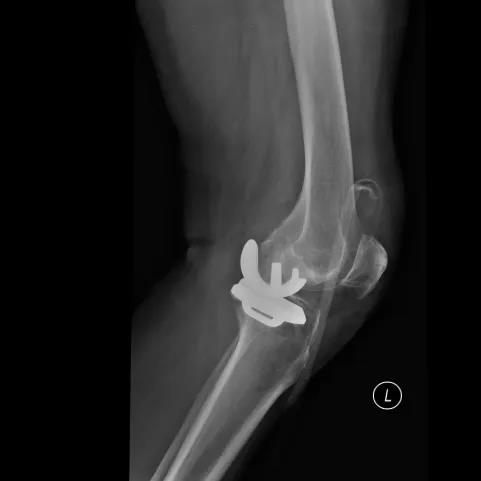

▲术前

▲术后